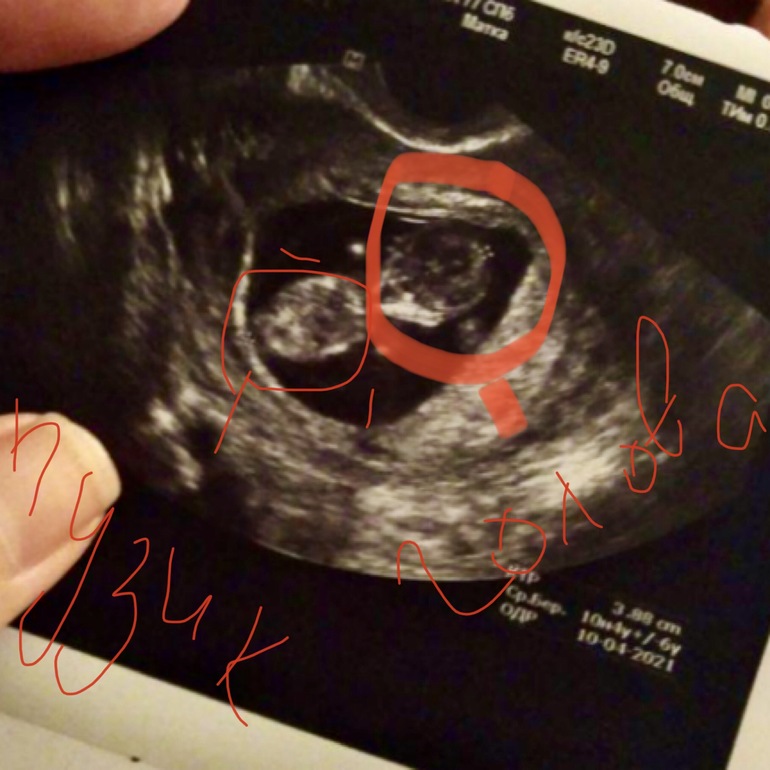

УЗИ, КТГ, доплерДоброго времени суток.Скажите пожалуйста у меня 10 недель, а на УЗИ есть плод размером с мандарин, но почему нету ручек и ножек, просто два пузыря... Или я просто накручиваю себя🤔🤔🤔

Ахах) Я тоже так сходила в 10 недель на неудачное узи. В чате все девочки выкладывали классные снимки со своими креветочками (как они их называли), там видно было и ручки и ножки. А мне дали смазанный снимок и там вообще ничего непонятно! Я пишу, почему у всех креветочки, а у меня колобок какой-то?) Но видимо вертелся, не хотел сниматься. Даже на экране ничего непонятно было плюс ещё и тонус сжал пя.

Вот что это? Яйцо в яйце, блин! Вышла расстроенная, думаю зачем столько денег отдала. Не могла даже срок высчитать долго🤦♀️

У вас тут как раз все понятно. Малышок лежит на спине прям лицом к вам. Даже немного видно ручки)

о, да у вас тут все видно))) пхх. точечки белые - это ножки и ручки были на вас направлены, поперечный срез. это голова и туловище) только мне кажется что голова слева. но я по узи вообще ламер, тут девочки на таком сроке даже пол умеют определять))))

Ребенок скорее всего лежал спиной к вам) потому только голова и туловище видны)))